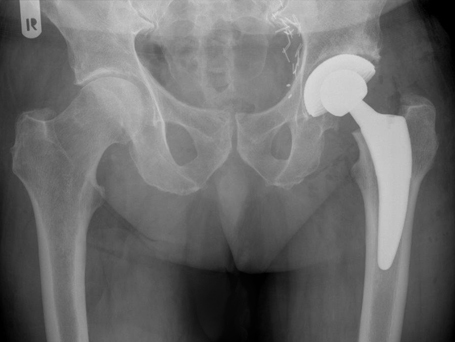

HÜFT-TEP DES PATIENTEN

Linksseitiger Hueftgelenksverschleiß

Postoperatives Kontrollbild